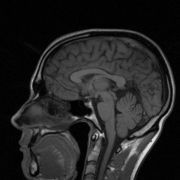

Magnetic resonance image showing a median sagittal cross section through a human head.